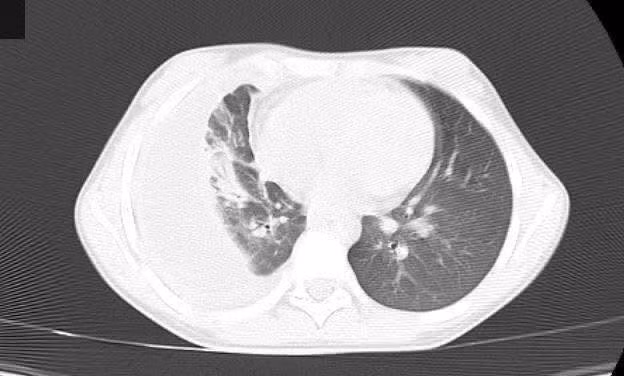

viem-mu-mang-1.jpg

Viêm phổi trên phim chụp cắt lớp vi tính - Ảnh BVCC